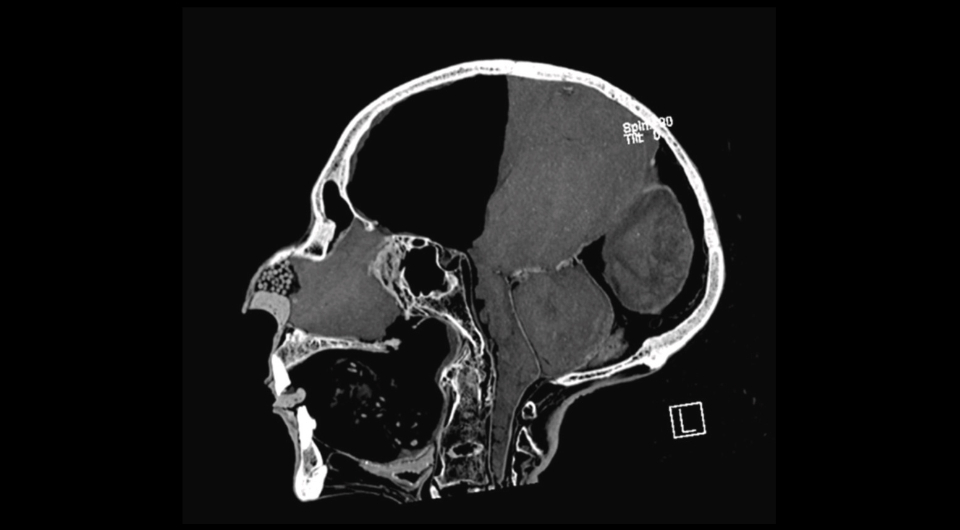

Комп'ютерна томограма черепа Рамсеса ІІ

Caroline Wilkinson et al. / Journal of Archaeological Science, 2023

Керолайн Вілкінсон (Caroline Wilkinson) з Ліверпульського університету імені Джона Мурса спільно з колегами з Великобританії та Єгипту повторно досліджувала останки Рамсеса II, щоб реконструювати зовнішність цієї людини для французького документального фільму, спираючись на сучасні методи діагностики та візуалізації. Для цього вчені зробили комп'ютерну томографію муміфікованого тіла царя, щоб потім збудували тривимірну модель його голови.

Проаналізувавши комп'ютерні томограми, палеорадіологи підтвердили, що вік фараона на момент смерті справді становив близько 90 років. На знімках також поганий стан зубів цієї людини, частина з яких була відсутня. Крім того, біля кореня другого моляра дослідники помітили великий абсцес. Вчені також виявили, що бальзамувальники намагалися зберегти форму носа царя, для чого засунули йому всередину невелику кістку, дрібне насіння та смолу.